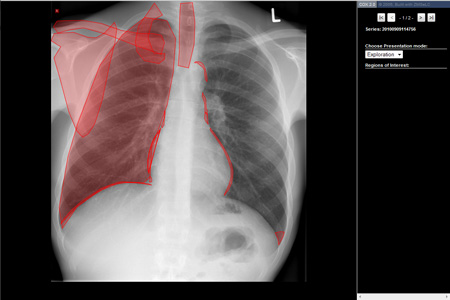

Der Modus „Exploration“ bietet eine schnelle Übersicht über die im Bild vorhandenen anatomischen Strukturen (siehe Abb. 2).

Abb.2 „Exploration“ Röntgen-Thorax mit Markierung aller anatomischen Strukturen